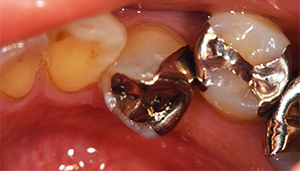

治療前

治療前 パノラマレントゲン写真

担当医師所見:

銀歯の詰め物の下で虫歯があり、神経を取り除く必要が高いことがわかります。

銀歯が多々奥歯につめられており、噛み合わせもきちんと見ていく必要があります。

奥歯の詰め物の治療終了後

奥歯の治療が終わったところです。前歯の治療に行く前に、噛み合わせをしっかり確認します。

治療後